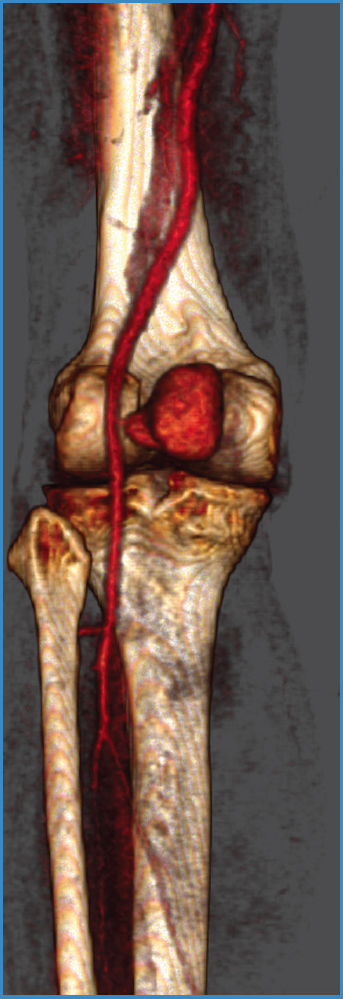

Se solicitó una ecografía-Doppler, en la que se observó una dilatación sacular adyacente a la arteria poplítea, de unos 50 × 30 mm, con flujo en su interior con el signo de ying-yang, que sugería un pseudoaneurisma. Se realiza una angiografía por tomografía computarizada (ATC) que confirma el pseudoaneurisma poplíteo de 40 mm de diámetro máximo y se localiza la rotura arterial a nivel de la segunda porción de la arteria poplítea (Fig. 1).

Figura 1. Angiografía por tomografía computarizada donde se aprecia voluminoso pseudoaneurisma poplíteo con un cuello pequeño y estrecho localizado en la 2.a porción de la arteria poplítea.